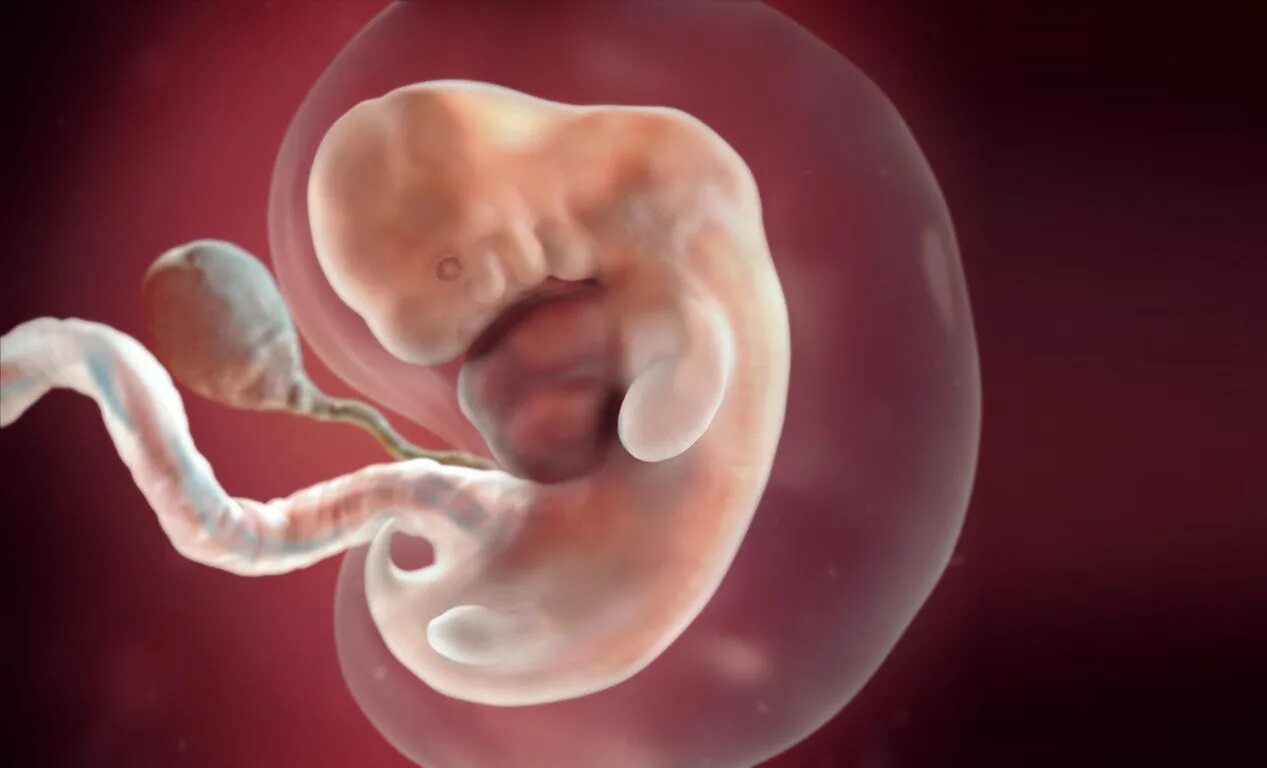

7 недель ощущения